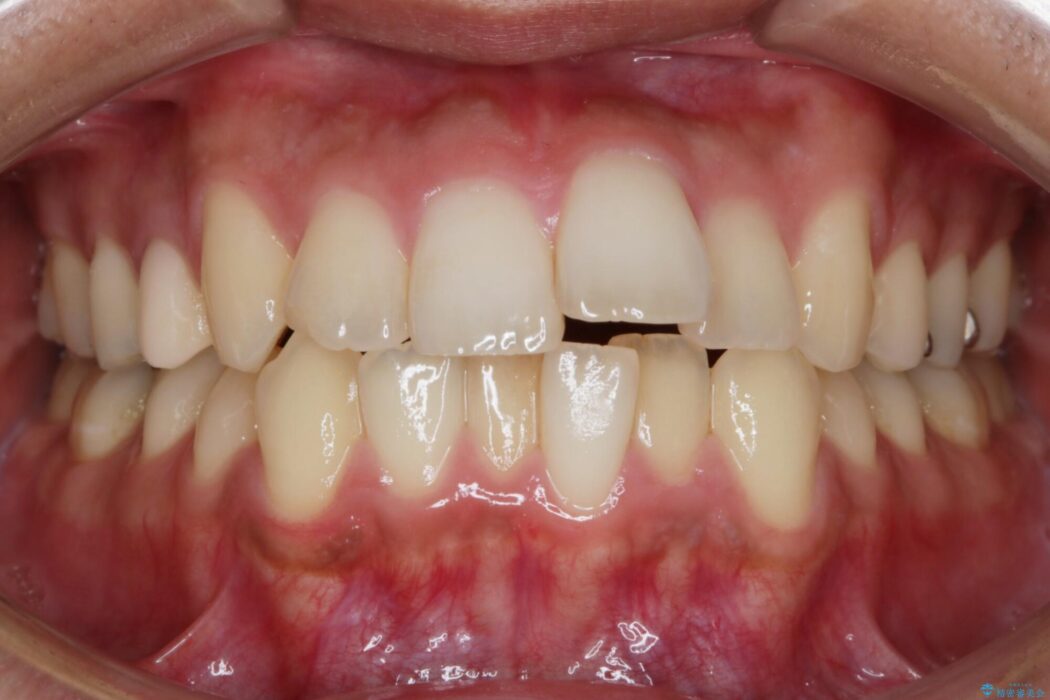

歯列のガタガタと飛び出ている前歯を治したいとのことで来院されました。

目立たない矯正装置をご希望でしたのでマウスピース装置(インビザライン)をご提案しました。

装置の範囲内で可能な限り前歯の位置を動かし整えるため、マイクロインプラントを用いて遠心移動をする歯列矯正を計画しました。